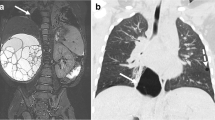

According to the qualitative imaging assessment included in the structured MRI report, CLA-related abnormalities were best seen on ZTE (airway), PROPELLER (vascularisation), and SPGR expiration (hypointense structures such as cysts, low attenuation regions, and hyperinflation) sequences. Six patients had an MRA FIESTA sequence available; this sequence was rated best to depict abnormal vascularisation in five patients. In one patient, the MRA FIESTA was insufficient due to severe movement artefacts. In two patients with a vascular component of the CLA, no MRA FIESTA sequence was made; however, abnormal vascularisation was sufficiently visualised on the T2-w PROPELLER sequence. An example of the visualisation of lesion vascularisation on postnatal CT compared to school-age MRI is shown in Fig. 6. Qualitative scoring showed acceptable quality for the ZTE sequence, with a median score of ‘above average’ for the visualisation of all lung structures (Table 4). The T2-weighted PROPELLER sequence scored ‘satisfactory’ but did show less noise/artefacts compared to the ZTE sequence.

Visualisation of lesion vascularisation on axial contrast-enhanced postnatal CT (a and d), MRA FIESTA (b and e), and T2-w PROPELLER (c and f) in a patient with BPS. Images show venous drainage of the lesion into the hemiazygos vein (thin arrow on a, b, c) and a bronchele (thick arrow on a, b, c) and arterial supply from the aorta descendens (arrow on d, e, f). BPS, bronchopulmonary sequester; CECT, contrast-enhanced computed tomography; MRA FIESTA, magnetic resonance angiography; PROPELLER, periodically overlapping parallel lines with enhanced reconstruction